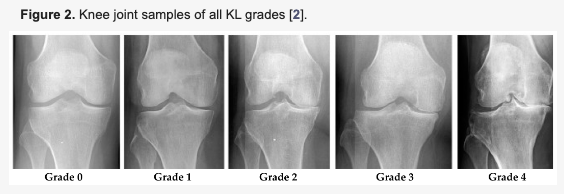

무릎 통증 중에 가장 큰 원인 중에 하나인 무릎 관절염에 대해서 더 자세하게 살펴 보겠습니다. 보시는 바와 같이 무릎 관절염은 엑스레이를 찍어서 진행정도를 알 수 있습니다. 위의 사진에서 뼈와 뼈(대퇴골과 경골) 사이에는 양 쪽에 연골이 들어가 있습니다.

이 연골의 역할은 우리가 걷거나 운동을 할 때 오는 충격을 흡수하는 것 입니다. 그리고 사진상에서 안 좋아질 수록 그 공간이 불규칙해지고 더욱 좁아지는 것을 알 수 있습니다. Grade 5의 경우 아예 한쪽은 뼈끼리 맞닿는 관절염 말기의 모습을 볼 수 있습니다.